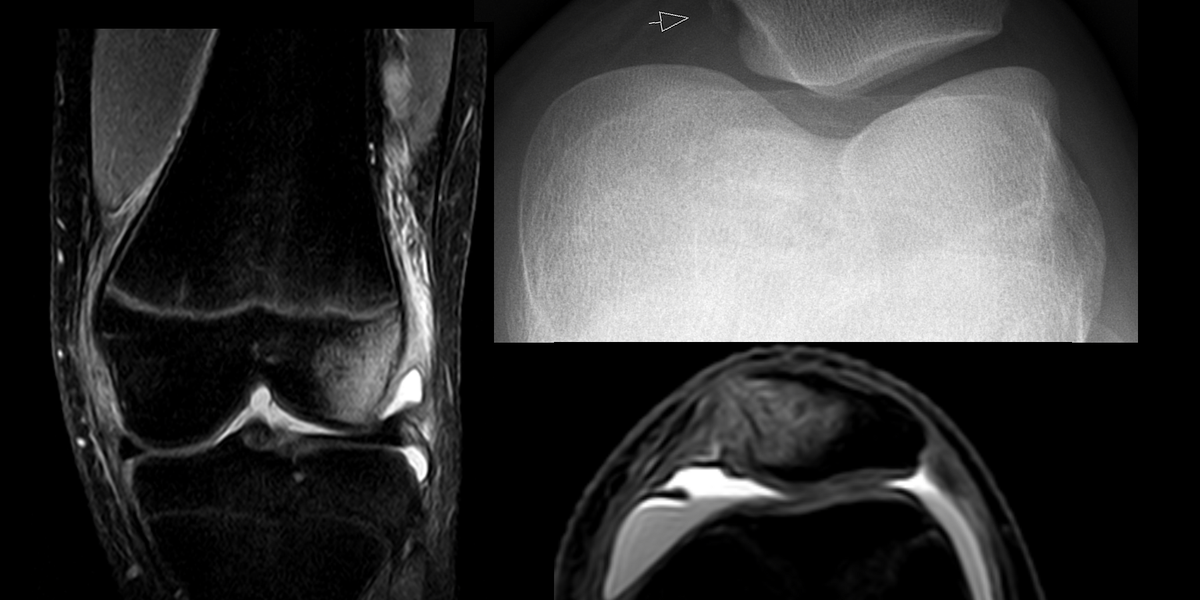

Patella

The patella is the largest sesamoid bone, embedded in the quadriceps tendon over the knee. It acts as a lever to improve knee extension and protects the joint. It’s clinically important for fractures and anterior knee pain.